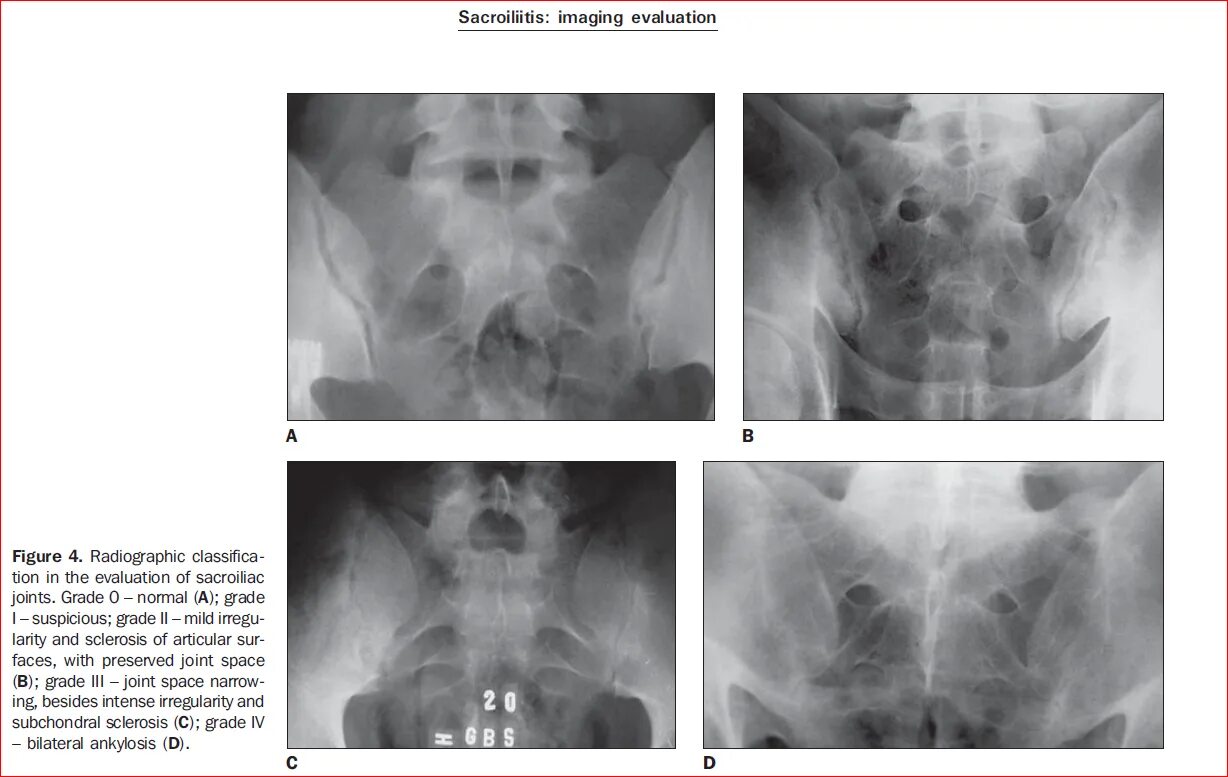

Сакроилеит рекомендации